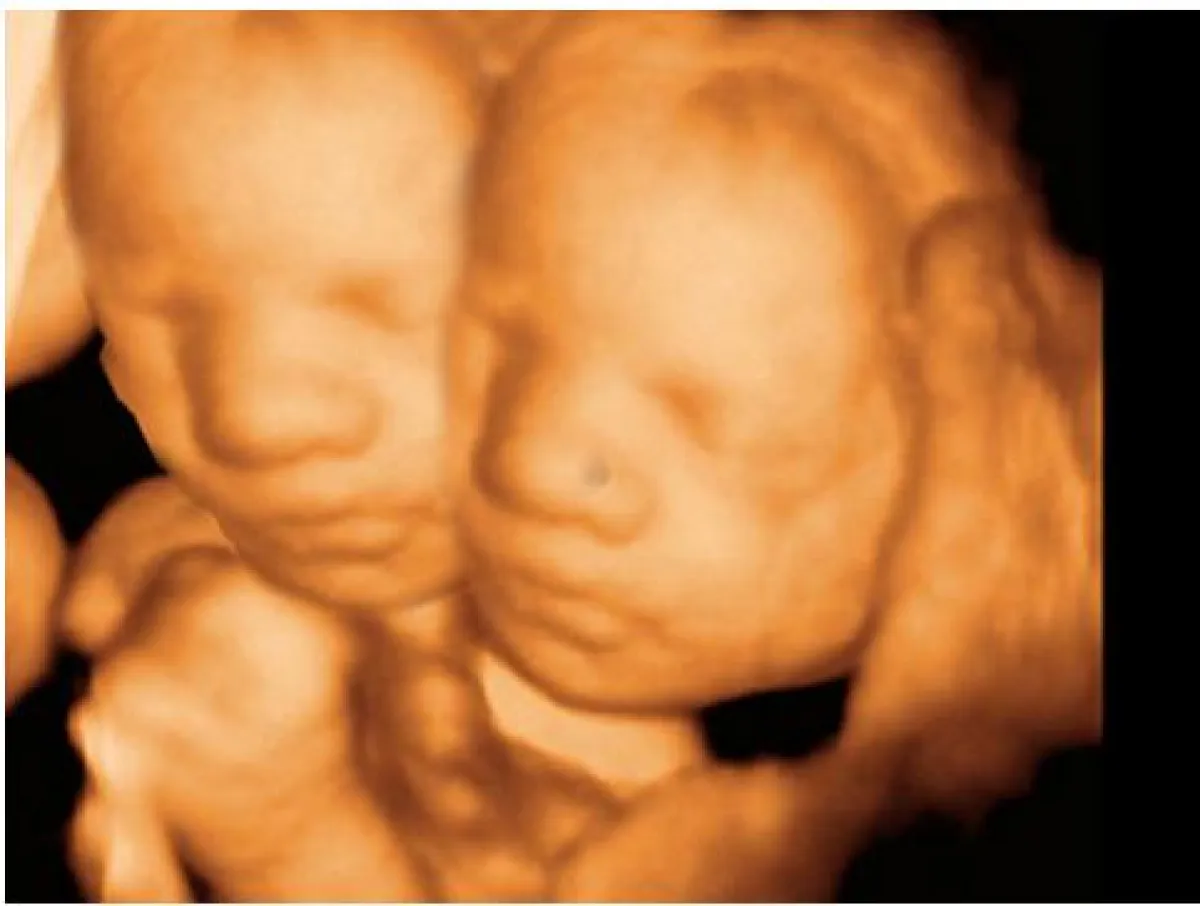

لم تستطع امرأة أسترالية أن تجري عملية إجهاض لجنينها بالرغم من أنه برأسين، ولا وجود أمل في بقائه على قيد الحياة بعد الولادة، على حسب قول الأطباء.

وتقول ريني من سيدني في أستراليا، وهي أم لسبعة أطفال: "قررنا أنا وزوجي عدم إجراء عملية الإجهاض مهما كلف الأمر، لأننا ضد فكرة قتل الطفل، حتى لو أصبحت ولادته عالة ومعاناة له وللعائلة بكاملها". كما يتفق معها زوجها بقوله:" إنّ قتل الطفل المعاق هو أسوأ من رفضه بسبب متلازمة التوحد مثلاً، وأريد أن أشهد ابنتي حتى إذا كانت ستعيش زمنًا قصيرًا جدًا".

الجدير بالذكر حدثت حالة مشابهة في إحدى مستشفيات ولاية (القضارف) بشرقي السودان، وهي ولادة نادرة الحدوث لولادة طفلة برأسين ولكن المؤسف هو موتها بعد 4 ساعات من ميلادها، برغم تأكيد مدير المستشفى بأنّ الطفلة بحالة جيدة ولا تعاني من أية أمراض، وذلك قبل وفاتها.